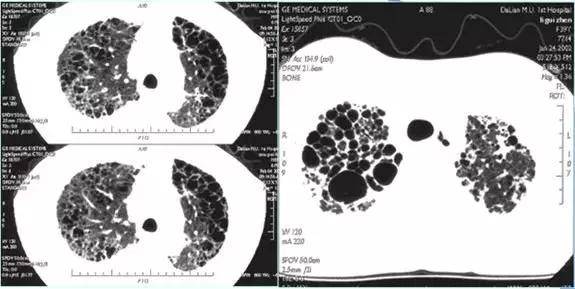

空腔病变

CT征象十:肺间质征与蜂窝肺

蜂窝肺表现为:两肺内大小数mm~数cm,壁菲薄的多发呈蜂窝状的透亮影,多见于肺间质纤维化病变的晚期。

肺间质纤维化晚期——两肺蜂窝影

两肺弥漫蜂窝影-肺淋巴管肌瘤病,均为女性